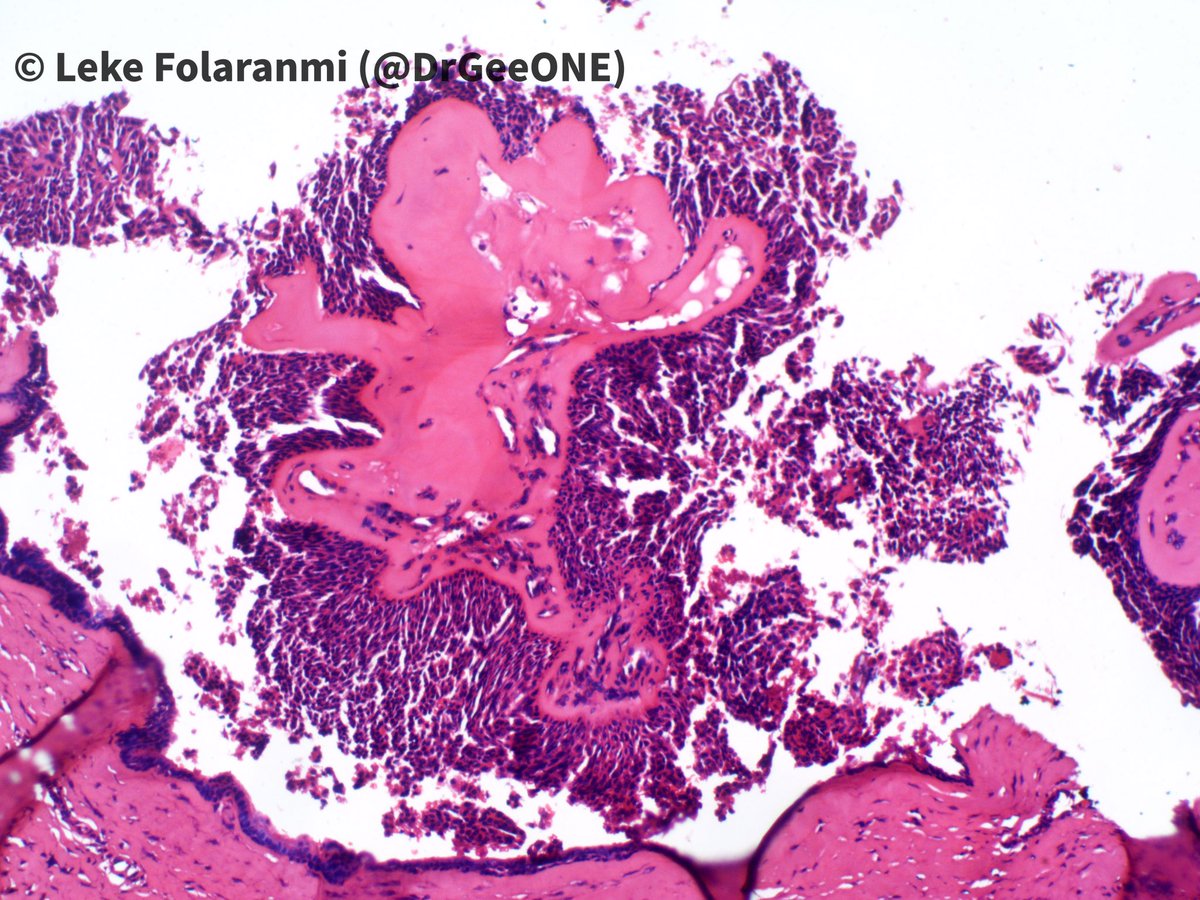

Nodular finger mass in a young female.

Duration: 2 years

I’m torn between 2 worlds: Nodular/cystic hidradenoma vs Aggressive Digital Papillary Adenocarcinoma.

What are your thoughts?